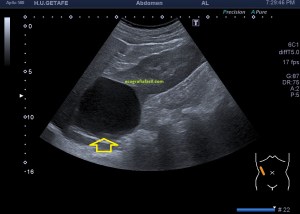

Es muy útil para lesiones que han crecido mucho y no podemos conjugar en una sola imagen, por ejemplo, un lipoma, cuando superan la medida de la huella de la sonda no son medibles, hay que usar «panoramic view», y como este caso, otros muchos.

En la imagen 3 ves una imagen de un lipoma, mide 7 cms, la huella de la sonda mide 5cms, la «panoramic view» posee una regla centimetrada que sigue el contorno de la imagen, justo en la profundidad de la misma y lo marca la flecha amarilla. La profundidad la marca la flecha roja y la flecha blanca marca el rango centimetral de los 5cms, fíjate que la línea blanca es ligeramente mayor cada 5 cms. Sirve de referencia, como en la imagen 4 donde ves una colección en el glúteo de más de 10 cms.